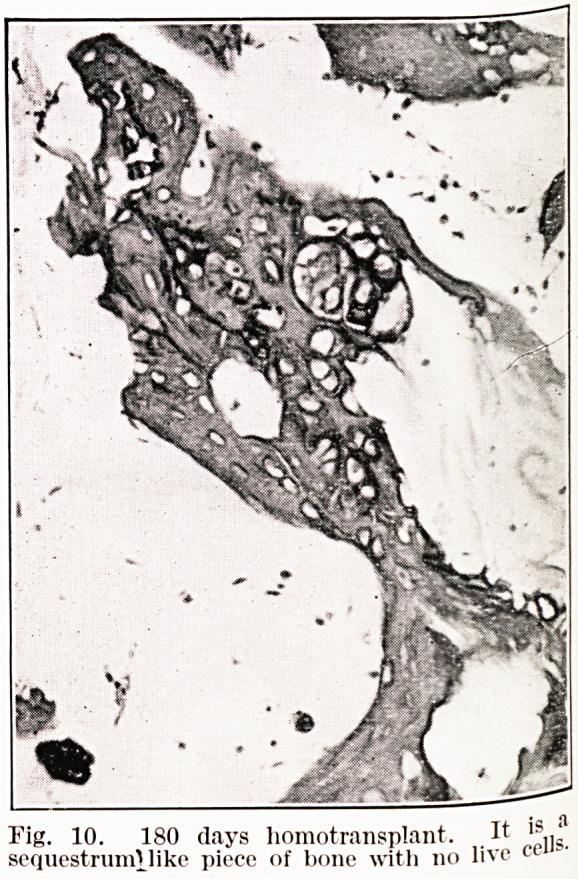

Observations on bone transplants in the anterior chamber of the eye.